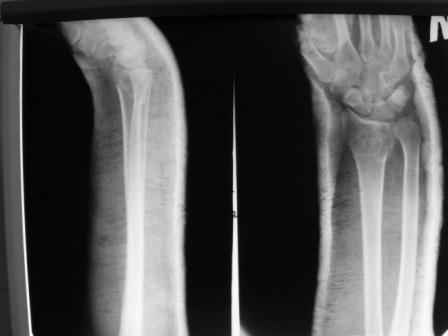

Уважаемые коллеги.Прошу обсудить случай лечения перелома дистального метаэпифиза лучевой кости. Ситуация скандальная и крайне неблагоприятная. Больная с патологической обстоятельностью мышления, склонностью к сутяжничеству, патологическими умозаключениями, не поддающимися коррекции (см. психиатрию, правда офиц. диагноза нет). В данном случае есть ряд ошибок с нашей стороны, прежде всего в отношении качества ведения документации (за что получил административное взыскание, по делом мне дураку). В остальном- придерживались в лечении подхода классический советской школы. Так как умную операцию…… сами знаете… 15.12- перелом луча в Москве. Там же репозиция, гипс. Дальнейшее лечение у нас в ЦРБ. 20.12.- вторичное смещение в гипсе21.12- под внутривенным наркозом- репозиция, гипсовая лонгета. Дальше начинается самое интересное. После репозиции больная заявила, что я (репозицию делал я) порвал ей все связки в суставе, посинел у нее 5 палец, якобы я за него тянул и т. д. На самом деле на 2 сутки после репозиции рука немного отекла и было незначительное сдавление гипсом, который был ослаблен. Дальнейшее лечение консервативное. Через 6 недель- гипс снят, назначено ЛФК. Пациентка крайне недовольна. Говорит, что на снимке у нее выступает кость, я ей сломал руку и.т.д. В общем началось. Пациентка прочитала в интернете наверное все, что есть по данной травме.По заключениями рентгенологов и консультанта из КДЦ областной больницы - стояние отломков допустимое. Объективно говоря- снижена высота лучевой кости, диастаз лучелоктевого сочленения, и не сросся шиловидный отросток. однако на РКТ при сравнении с другой стороной- разница незначительная. Дальше в одной из больниц нашей области и одной из больниц Москвы (вроде бы КГБ 53) врачи сказали, что репозиция сделана плохо. Нужна операция (восстановить длину лучевой кости), даже один из них предложил РЕДРЕССАЦИЮ (хи-хи) с наложением аппарата Илизарова. Что это для данной больной- радость неописанная. (см. описание психического статуса). Ничем другим, кроме зарабатывания дешевого авторитета объяснить данный факт не могу.Кстати, у больной еще нейропатия локтевого нерва.Для разрешения конфликта больная направлена на консультацию в ЦИТО на 03.03.11.

1. РЕПОЗИЦИЯ сделана качественно(ОСНОВНЫЕ 2 УГЛА ВЫСТАВЛЕНЫ ПРАВИЛЬНО ) , но перелом нестабильный и склонен к втор смещению . Поэтому мы стараемся все переломы со смещением фиксировать 3-МЯ спицами по GRIN методике .

2. По сравнению и без ! втор смещение незначительное.НЕТ НИКАКОЙ ,,локтевой косорукости,,маделунгов . но имеется смещение совести у врачей КГБ 35--НЕТ ЗДОРОВЫХ, есть только недообследованные ! Этому смещению аппарат внешней фиксации не поможет .Психопаткам в менопаузе да весной только этого и надо чуть толкнули и поехало .

1. Репозиция от 21.12.10 была выполнена лучше, чем первичная.

2. Укорочение лучевой кости с изменениями дистального лучелоктевого сустава требует оперативного лечения

Заключение: Консолидированный в неправильном положении перелом дистального метафиза левой лучевой кости. Ротационная контрактура левого предплечья. Рекомендовано- разработка, консультация через 2 месяца.

3.Исходя из конкретной ситуации и здравого смысла абсолютных показаний к операции не было и сразу после травмы и нет сейчас ,уже после сращения,поскольку перелом внесуставной,а осколок по тылу луча не препятствует торцевому упору по волярному краю луча.